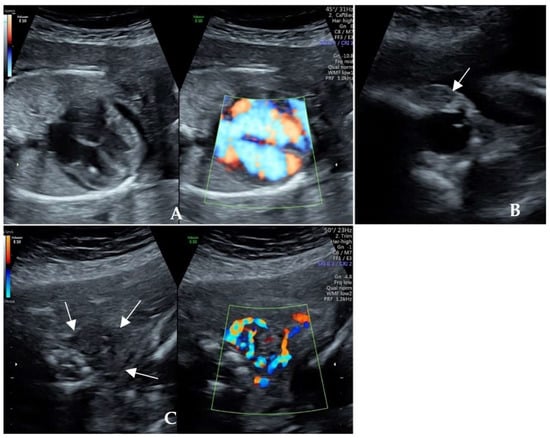

| Fetal manifestations | Fetal cardiac enlargement, pericardial effusion and cardiac hypertrophy, FGR, tachycardia, proptosis, and ventriculomegaly | Fetal tachycardia, enlarged heart and pericardial effusion, tricuspid regurgitation, oligohydramnios, and minor renal dysplasia |

| Fetal thyroid status | Thyroid diffusely enlarged with abundant blood flow, hyperthyroidism (TSH 0.018 μIU/mL and TRAb 32.74 IU/L) | Fetal thyroid gland congested, hyperthyroidism (TSH 0.09 μIU/mL and TRAb 31.9 IU/L) |

| Intrauterine treatment | Maternal oral administration of methimazole from 22+ weeks of gestation | Maternal oral administration of methimazole from the 23+ week of gestation. |

| Significant signs of response | The fetal heart rate returned to the normal range 10 days later. The pericardial effusion and cardiothoracic ratio were relieved. | The fetal heart rate returned to normal at the 26th gestational week. Oligohydramnios, cardiac enlargement, pericardial effusion, and thyroid hyperemia were resolved. |